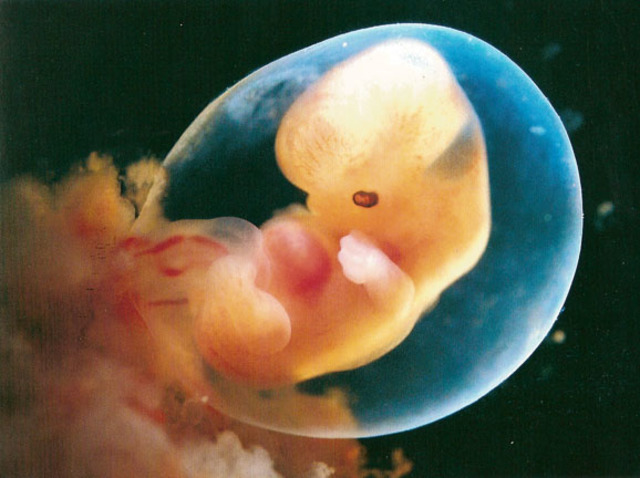

• 2 MESES

2 MESES

el feto medirá entre 1,4 y 1,8 centímetros. Ya tiene párpados, labio superior y nariz y orejas se están empezando a formar. El cuerpo se está alargando, pueden reconocerse lo que serán brazos y piernas, y es posible ver el esqueleto a través de su piel, que es translúcida. El esqueleto está formado por un cartílago suave todavía, no son huesos. Los órganos como el corazón y el hígado funcionan y siguen especializándose.